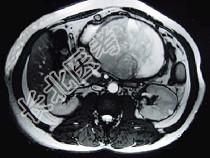

- 单项选择题男,36岁, 腹胀、消化不良、消瘦、中上腹痛,影像检查如下图, 最可能的诊断为 ( )

A、胃间质瘤并肝血管瘤

B、胃淋巴瘤伴原发性肝癌

C、胃间质瘤并原发性肝癌

D、内胚窦瘤肝转移

E、胃间质肉瘤并肝转移